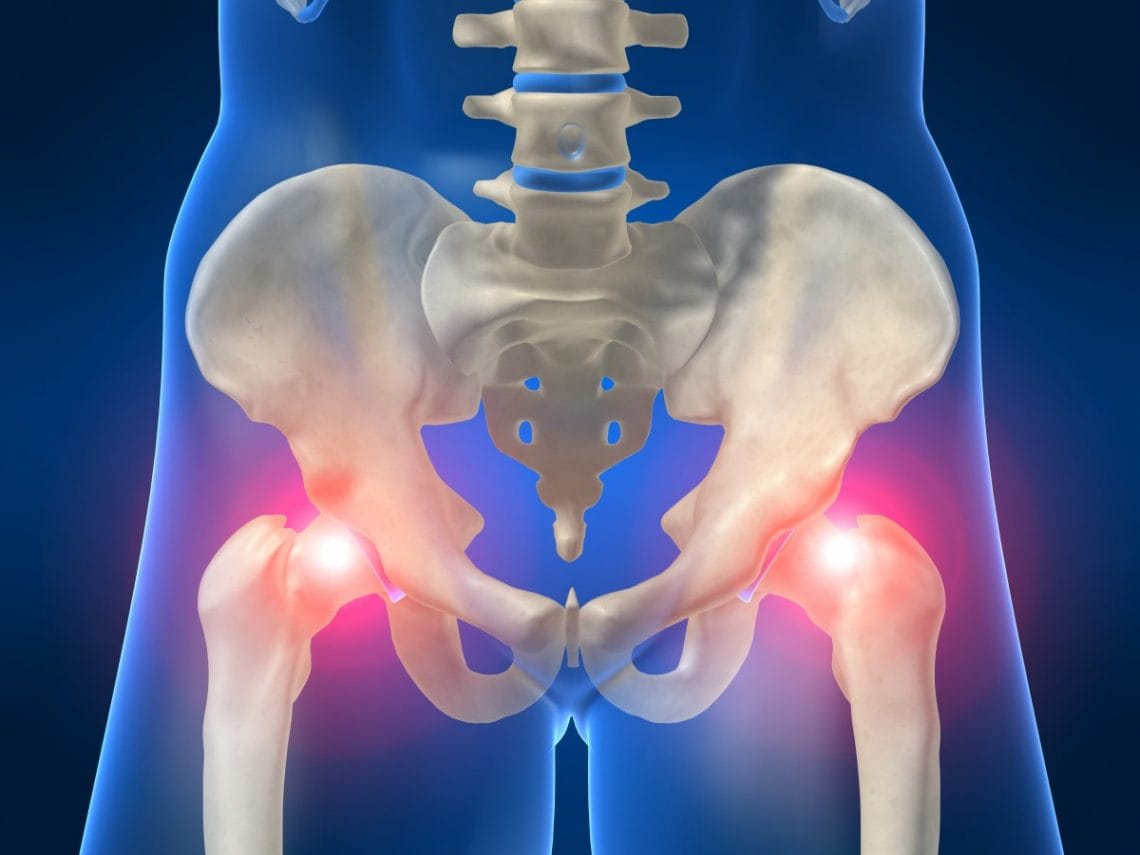

مفصل الحوض أو ما يسمى بمفصل الورك هو أقوى وأكبر المفاصل التي توجد في جسم الإنسان وهو المفصل الذي يربط بين عظمة الحوض والفخذ، ولهذا السبب عند إصابة هذا المفصل بالتهابات أو أي مرض في هذا الوقت يشعر المريض بالعجز بسبب عدم قدرته على الحركة، مع العلم أن هذا التهاب يصاب به الشخص بشكل تدريجي ولكن في حالة إهمالة وعدم معالجته في المرحلة الأولى له يترتب على ذلك إصابة المفصل بالخشونة، وهي تعد من أصعب الأشياء التي من الممكن أن يعاني منها أي شخص، وعلى الرغم من قوة هذا المفصل إلا أنه يتأثر بأي حادثة أو يكسر يتعرض إليه.

وفي حالة الإصابة بالتهاب مفصل الحوض لا يتوقف الشعور بالألم عند هذا المفصل فقط ولكن الأمر يصل إلى منطقة أسفل الظهر والركبة والفخذين أيضًا، مع العلم أنه لا يشترط أن تكون الإصابة مباشرة لكي يحدث التهاب في مفصل الحوض ولكن توجد أسباب أخرى تكون سبب في التهاب هذا المفصل مثل ( التهاب الفقار اللاصق، التهاب العمود الفقري، التهاب المفاصل الروماتويدي، التهاب المفاصل الصدفية)، حيث تؤثر كل هذه المفاصل بشكل أو بآخر على مفصل الحوض والمشاكل الصحية التي من الممكن أن تترتب نتيجة التهاب المفصل نفسه.

- من أولى الأعراض التي يعاني منها الجميع هو الشعور المستمر بالألم شديد في منطقة الحوض، مع العلم أنه يكون في البداية بسيط وغير مستمر ولكن في حالة عدم الاهتمام به ومعالجته يزداد الأمر سوء يومًا بعد يوم وخصوصًا عند محاولة الوقوف وصعود السلم والمشي لفترات طويلة مع حمل أشياء ثقيلة.